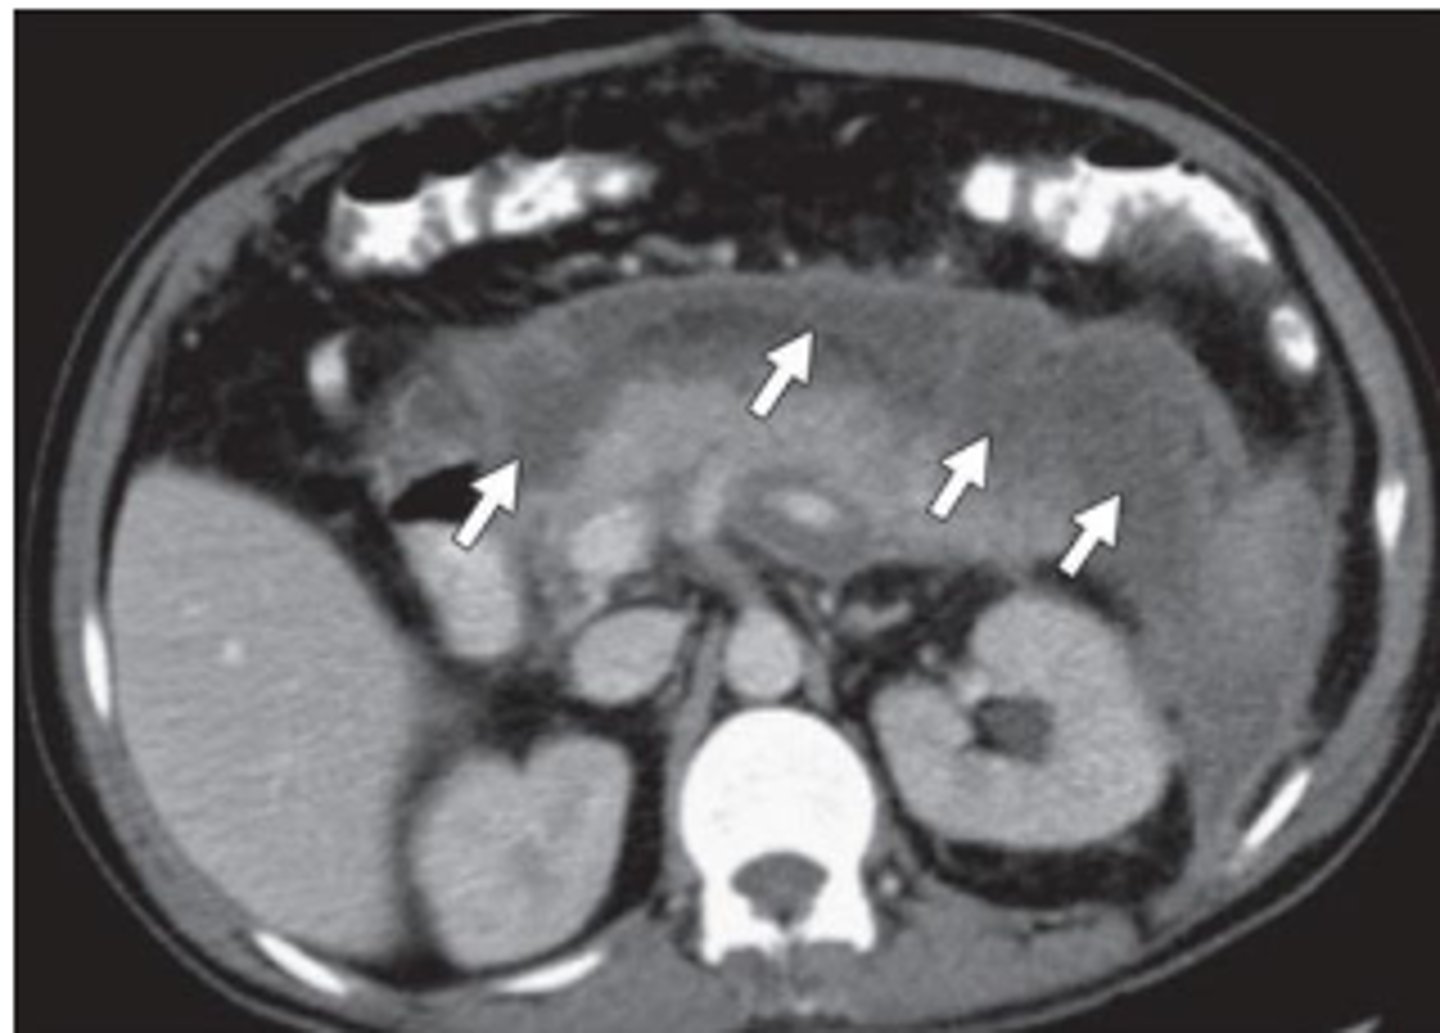

pancreatitis

inflammation of pancreas, often related to biliary tract disease or alcohol intake

Sx: abrupt onset deep epigastric pain w/ radiation to back, N/V, sweating, weakness, abdominal tenderness and distention, fever

Labs: leukocytosis, increased serum amylase, increased serum lipase

pancreas imaging

xray- may show calcified gallstones, localized ileus

US- not helpful in acute pancreatitis, may identify gallstones

CT- differentiating pancreatitis from other possibilities, enlarged pancreas

pancreatitis imaging

may appear enlarged and irregular, infiltration of peripancreatic fat, fluid surrounding